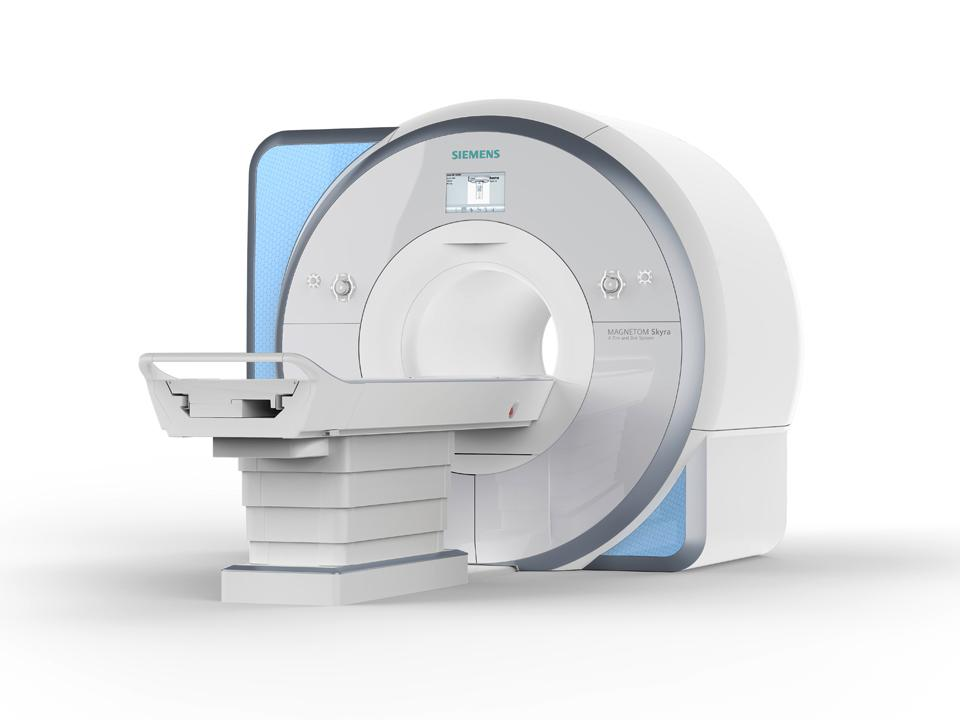

核磁共振MRI

原理简介

MRI的工作原理是共振人体的氢离子产生共振来产生图像。我们人体有很多H2O,也就是水!所以,有水的地方氢离子多,反之则少,也就是说有水的地方核磁共振做得清楚,没水的地方就做得不清楚。因此人们也戏称它是摇一摇再看的检查。

应用

擅长检查软组织

优点

辐射很小,没有骨性伪影,能多方面、多参数成像,有高度的软组织分辨能力;

缺点

检查时间长,费用相对高;

磁共振设备举例

dr在彩超什么意思一文搞懂X线、CT、MR、彩超检查的区别_https://www.jmylbn.com_新闻资讯_第15张